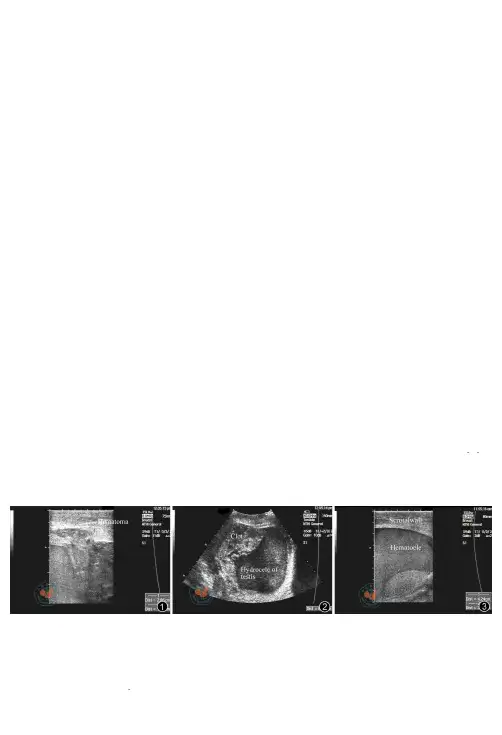

通过病史、体检,开放性损伤诊断明确,闭合性损伤18例通过彩色B超确诊,2例经驻地医院CT扫描确诊。

结论随着医学技术的进一步提高,对任何阴囊、会阴外伤均应考虑睾丸损伤的可能,及早进行超声和CT检查,可早期明确诊断,为手术探查赢得时间,避免延误病情。

1.2临床表现: 闭合性损伤后均有睾丸剧烈疼痛,恶心,呕吐,2例伴休克。

体检:睾丸肿大,触痛明显,酷似附睾睾丸炎6例;阴囊或(和)腹股沟区青紫,睾丸轮廓不清,透光实验阴性10例,4例因阴囊肿胀、鞘膜腔积血、疼痛拒检等因素,睾丸、附睾和精索的轮廓触摸不清楚。